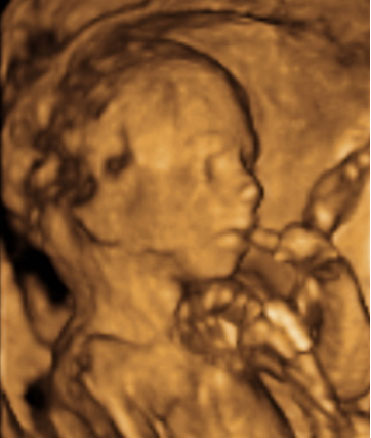

Ecografía Embarazo 2D y 3D - SEMANA 20